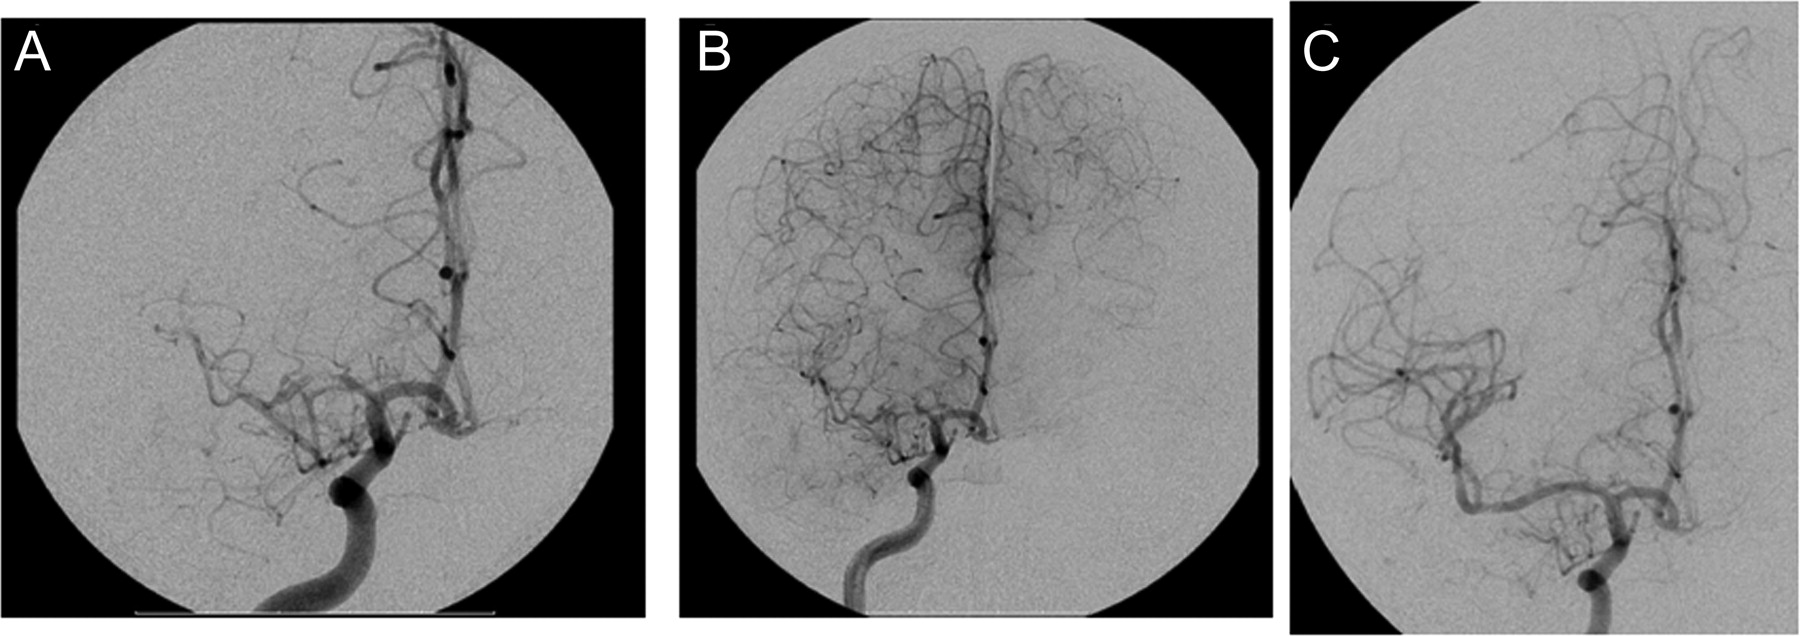

实验室测试包括一个完整的血细胞计数、血清化学、凝固面板,肝功能测试是正常的。心电图显示正常窦性心律和左心室肥大的证据。核磁共振成像显示,没有证据表明急性颅内异常;一种慢性左小脑梗塞是(图1)。CT血管造影显示严重双侧大脑中动脉(MCA)狭窄,更糟糕的是在右边,以及一个没有左椎动脉由传统血管摄影证实(图2一个)。

除了高总胆固醇(190 mg / dL)和低密度脂蛋白(130 mg / dL)的水平,评价是负数,技术包括负面结果超声心动图,血凝过快面板,CSF分析、血清学检查,艾滋病毒检测,尿毒理学,外围涂片,镰状细胞筛选。24小时动态心电监测上没有发现心律失常。脑血管造影术显示中度到重度的右MCA狭窄和温和派左MCA狭窄(图2),没有急性解剖或潜在的血管病变血管痉挛的证据。决定治疗与药物治疗病人。阿司匹林是停止,病人是放在氯吡格雷,辛伐他汀,低剂量氨氯地平与没有症状的复发。

重复MRI没有显示新的梗塞的证据。重复血管造影(图2B)证明恶化MCA狭窄。

病人现在已经进步灌注不足的症状,可参考的症状性颅内狭窄,尽管最佳医疗管理,介入管理被认为是。病人接受的翼展self-expandable支架放置正确的MCA (图2C) 2周后SPECT和认知测试。乙酰唑胺脑SPECT重复3天poststent显示改善皮质灌注没有受损的血管储备的新领域图3B)。4周后,重复神经心理测试显示完整的认知功能(平均或更好),包括正常的视觉空间技能,语言学习、记忆和执行功能,除了轻微的缺陷与受益于复杂的视觉记忆检索识别信号。这种患者的颅内疾病的潜在病因仍然不明。